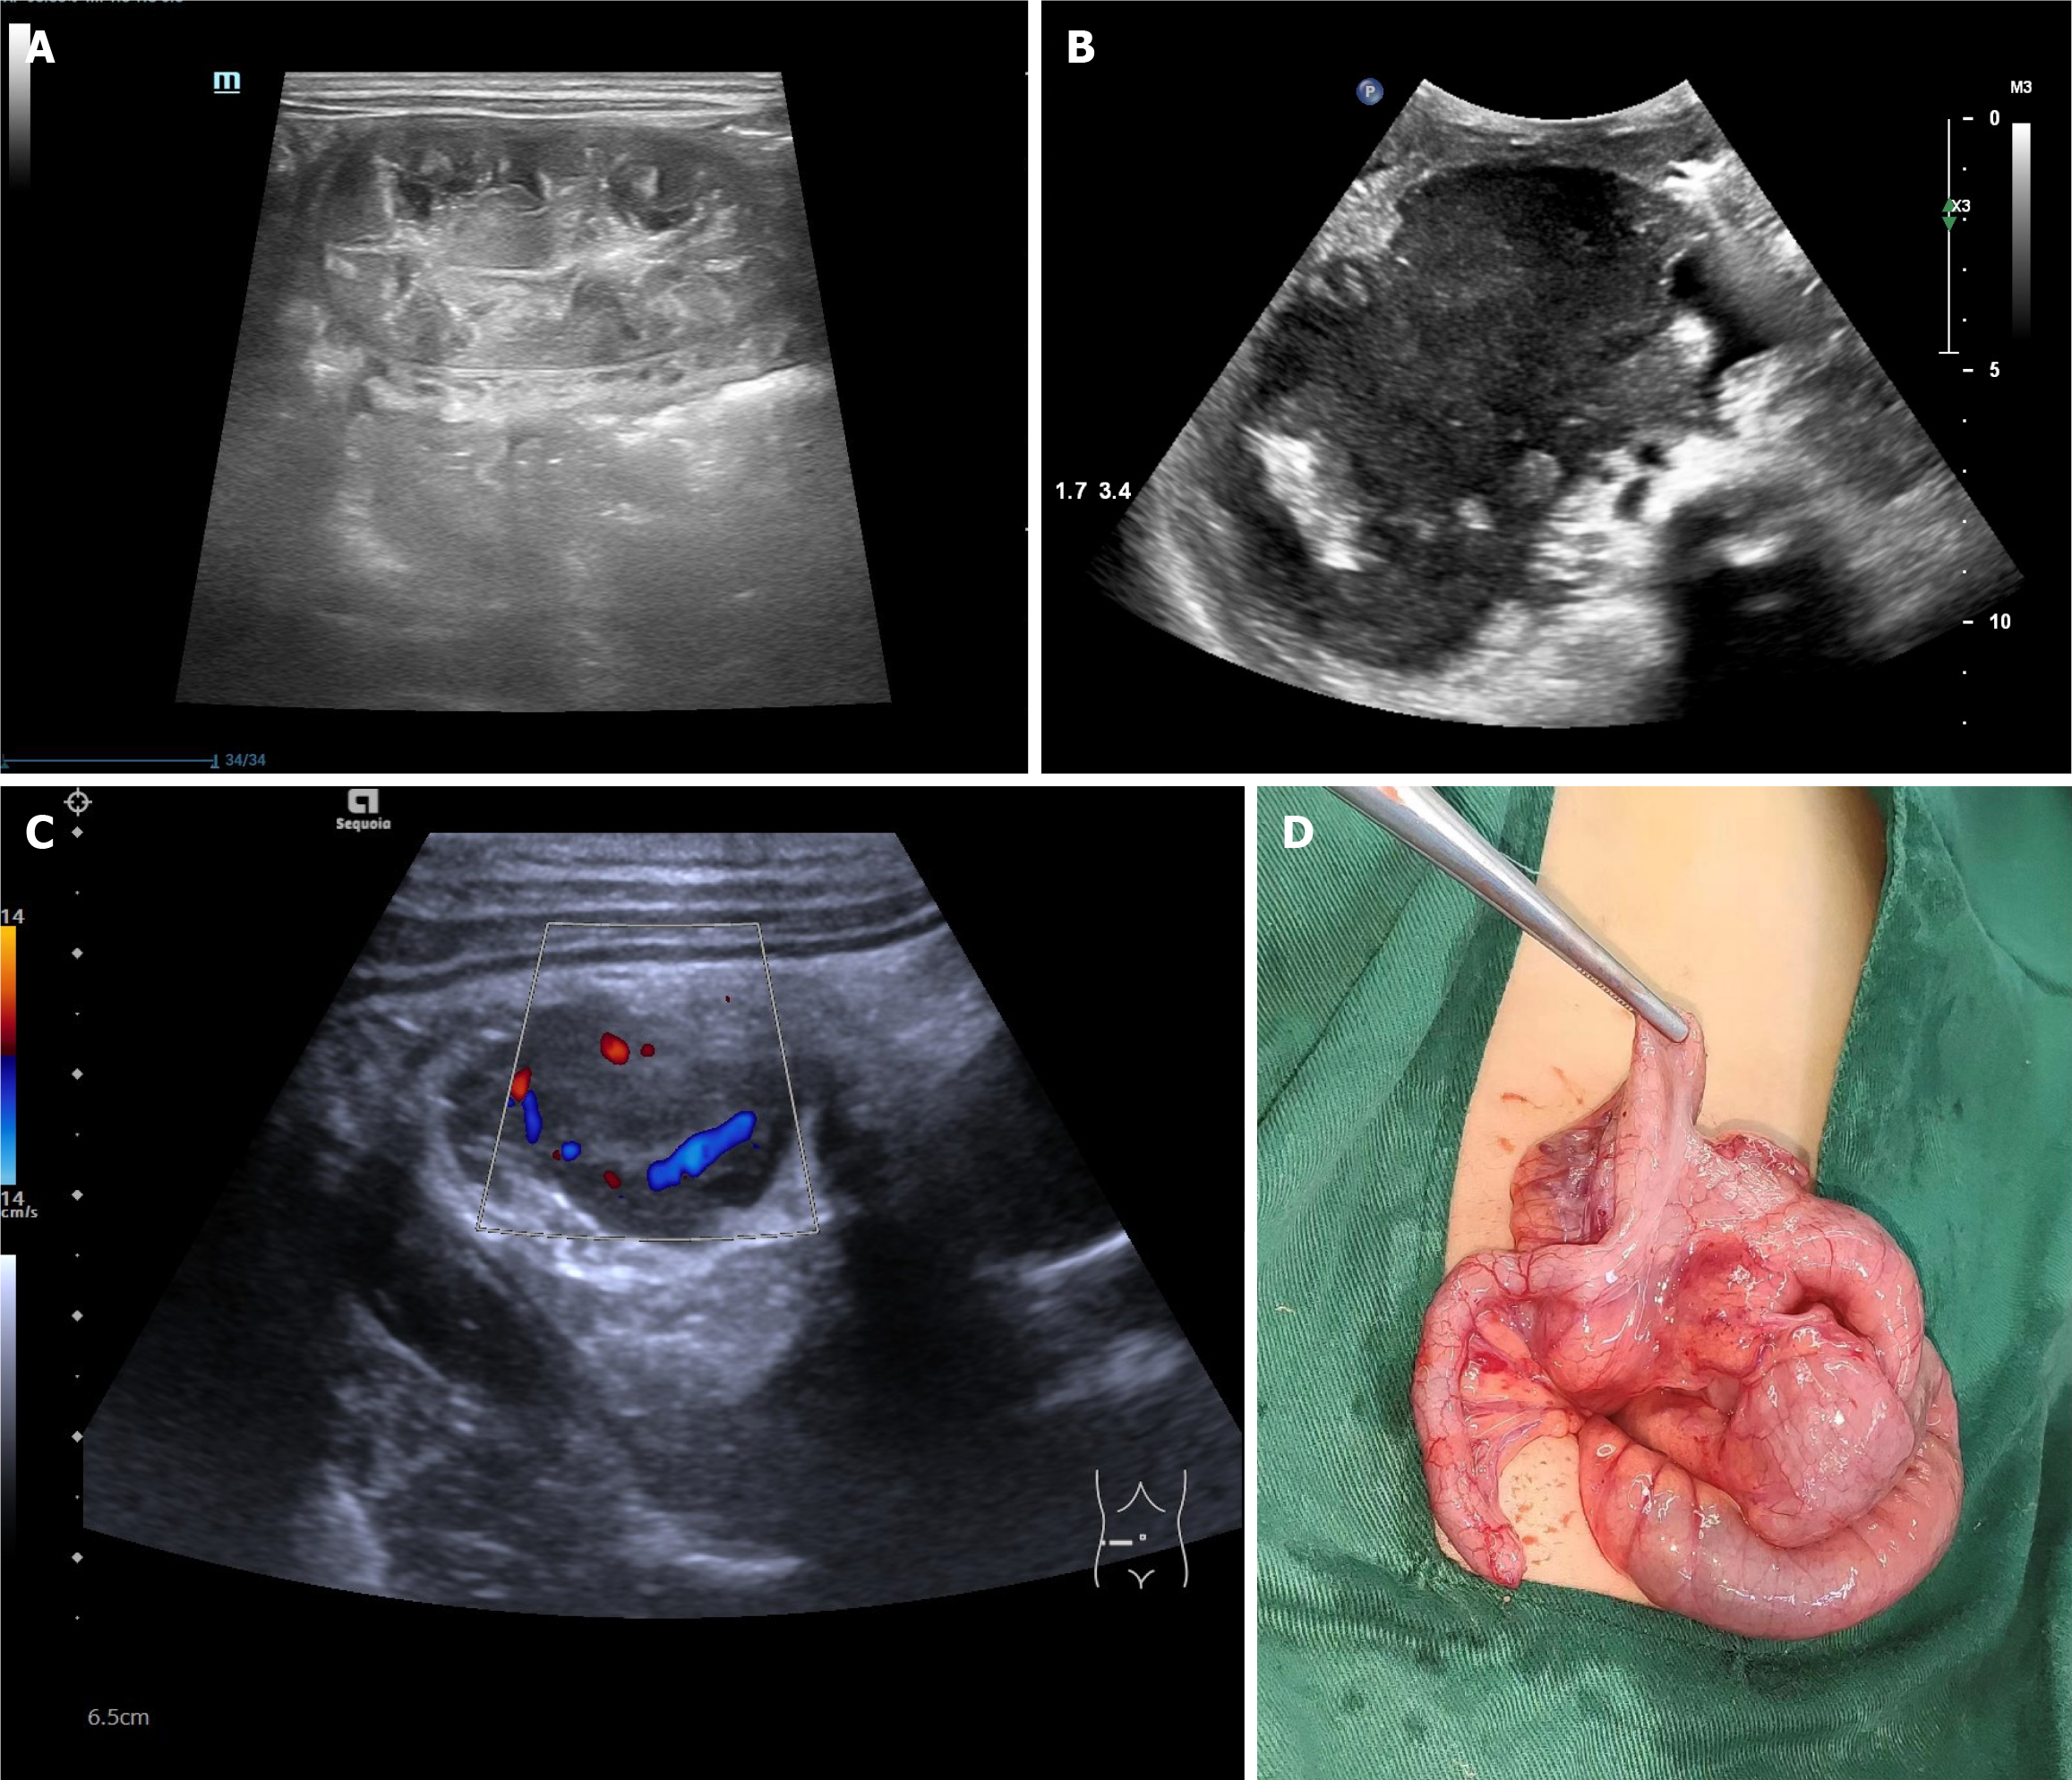

Figure 1 Ultrasound manifestations of the intestinal wall in intestinal lymphoma.

A: Focal segmental concentric annular thickening of the intestinal wall; B: Focal segmental the intestinal wall was eccentrically tumor-like thickened; C: Focal segmental solid masses of the intestinal wall to intussusception; D: Surgical photo.